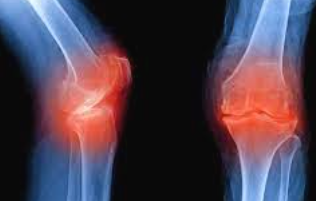

관절염과의 관계

무릎 연골 손상이 진행되면 결국 퇴행성 관절염으로 발전하게 됩니다. 초기 연골 손상 증상이 관절염의 전단계 증상으로 볼 수 있으며, 조기 발견과 치료가 관절염 예방에 매우 중요합니다.